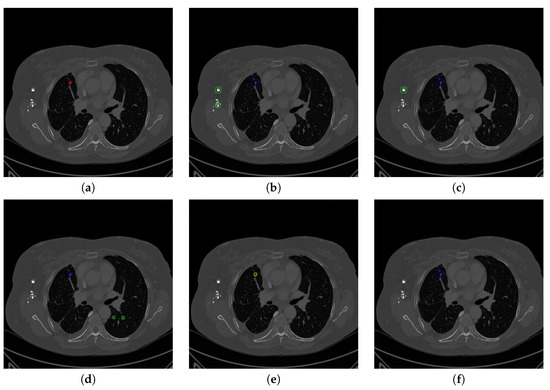

Figure 15 shows the results of detecting pulmonary nodules of using different network modules and different loss functions, including: (1) MSE loss only, (2) MSE-perceptual loss, and (3) MSE-perceptual-dice loss. Using only MSE as loss function results in failure detection of nodules with small sizes and irregular shapes. Without dice loss, the MSE-perceptual loss cannot differentiate the nodule candidates with quite small sizes because the number of pixels belonging to nodule candidates are much smaller than those belonging to background region. In contrast, combining the MSE, perceptual and dice loss can find both large and small nodule candidates, and achieve a good balance in taking the sizes and shapes of the candidates into the account of identification. Furthermore, training the three sub-networks as a uniform framework can enhance the inherent relation and co-operation of these three sub-networks in nodule detection and classification. The accuracy, sensitivity and specificity results shown in Table 7 confirm the above observation.

Figure 15.

The results of detecting pulmonary nodule through the proposed network with different loss strategies. Columns from left to right are: input images, detected nodule candidates, detected nodules. Rows from top to bottom are: ground truth detection results, nodule candidates and nodule detection by the proposed network with MSE loss, MSE-perceptual loss and the MSE-perceptual-dice loss.